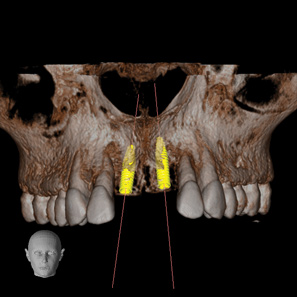

Fig 2. CBCT images: axial (Fig 2) and cross-sectional (Fig 3) views, and 3D reconstruction view (Fig 4) with virtually planned implant Nos. 8 and 9.

Figure 2

Fig 3. CBCT images: axial (Fig 2) and cross-sectional (Fig 3) views, and 3D reconstruction view (Fig 4) with virtually planned implant Nos. 8 and 9.

Figure 3

Fig 4. CBCT images: axial (Fig 2) and cross-sectional (Fig 3) views, and 3D reconstruction view (Fig 4) with virtually planned implant Nos. 8 and 9.

Figure 4